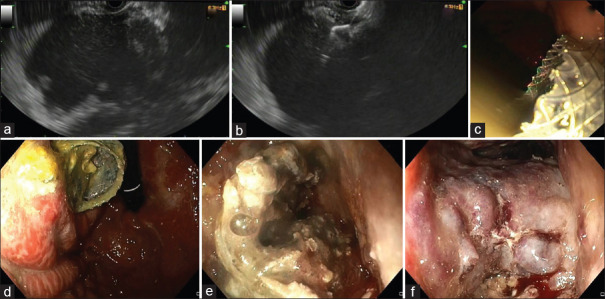

Abstract: Endoscopic ultrasonography (EUS) has progressed beyond diagnostic imaging to include EUS-guided tissue acquisition and EUS-directed therapies. This review provides an update on EUS-guided drainage and anastomotic procedures, and other therapeutic procedures. Today, EUS-guided drainage of symptomatic walled-off pancreatic fluid collections is the norm, with endoscopic necrosectomy as an adjunct. For high-risk surgical patients unsuitable for cholecystectomy, EUS-guided gallbladder drainage of acute cholecystitis is an option. Additionally, EUS-guided drainage of obstructed biliary and pancreatic ductal system can be performed as salvage procedures after unsuccessful endoscopic retrograde cholangiopancreatography (ERCP). Bariatric procedures such as Roux-en-Y gastric bypass alter the gastric anatomy, hindering access to the major papilla. This can be overcome by creating a conduit through the excluded stomach using EUS-directed transgastric ERCP. Gastric outlet obstruction and afferent loop syndrome can be treated using EUS-guided gastrojejunostomy. These therapeutic interventions are a major advancement in the field of interventional EUS, achieving significant clinical impact.